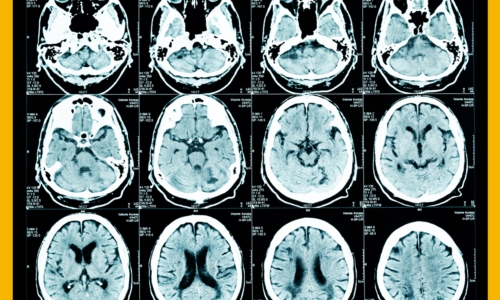

신체가 건강해도 뇌에 문제가 생기게 되면 신체 기능을 제대로 할 수가 없게 됩니다. 뇌 손상으로 제한된 신체 기능은 치료를 마친 후에도 회복이 제대로 되지 않거나 장애로 남는 경우가 많은데 뇌조직이 괴사되며 발생하게 되는 뇌경색이 대표적입니다. 과거에는 뇌출혈 환자가 많았지만 현재는 전체 뇌졸중 환자의 약 60~70%가 뇌경색 환자인 만큼 뇌졸중에서도 뇌경색이 차지하는 비중이 크다고 합니다.

건강보험심사평가원 자료에 따르면 뇌출혈로 병원을 찾은 환자보다 뇌경색으로 내원한 환자가 5배 이상 많았다고 하는데요 뇌경색은 뇌로 통하는 혈관이 막히면서 뇌 조직이 점차 괴사하게 되는 질환으로 날씨가 추워지는 겨울철에 특히 발생 가능성이 높은데요 혈관이 수축 하게 되면서 혈압 상승으로 이어지면서 뇌혈관 질환이 발생하게 되기 때문입니다.